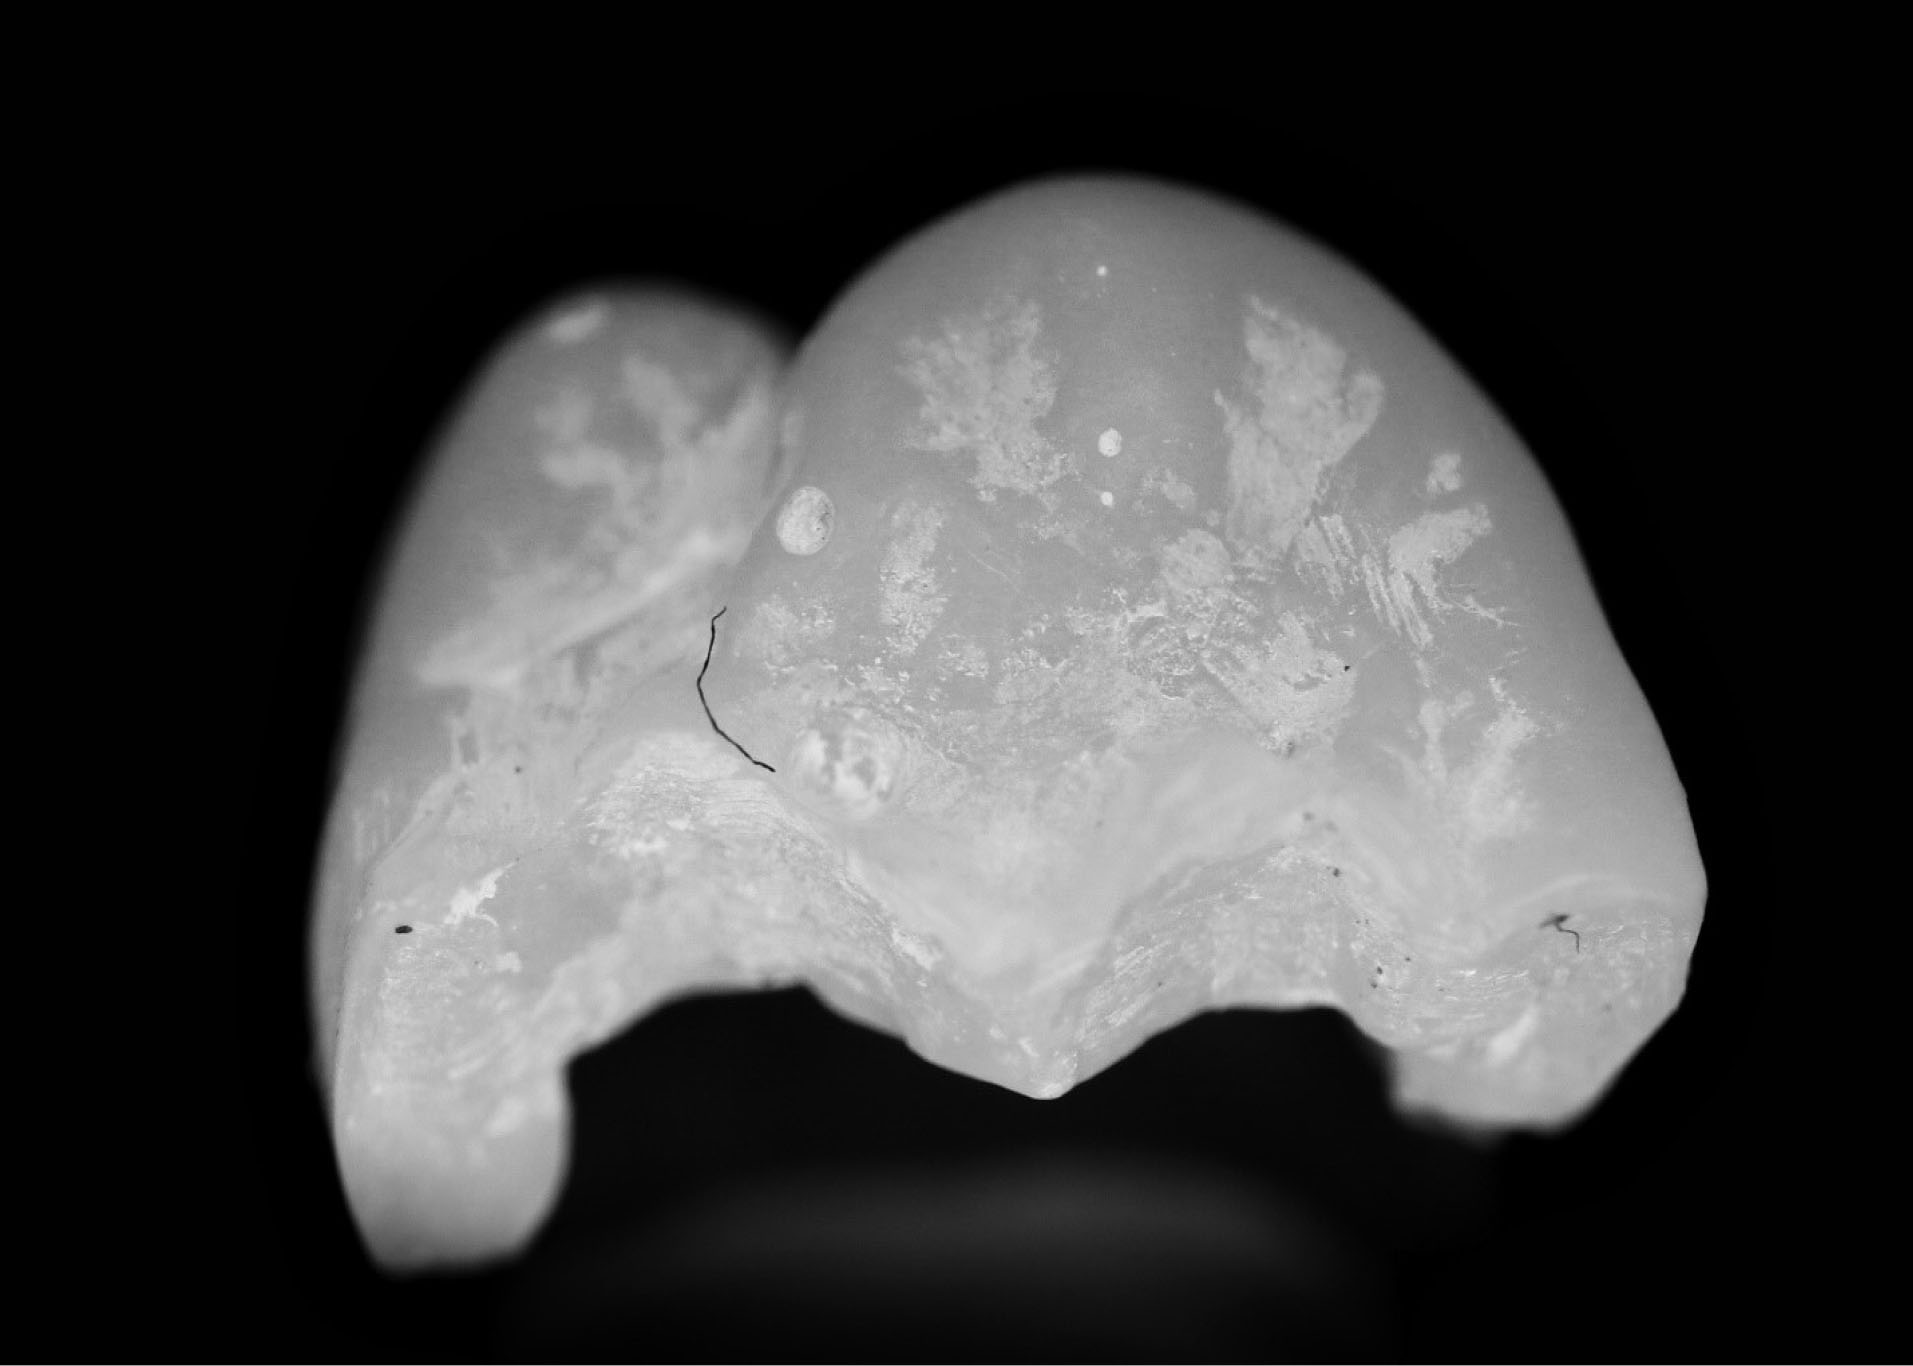

Although this study investigated indirect restorations with cobalt-chromium, other metal powders currently employed in additive manufacturing could be utilized, including stainless steel and titanium. 7 Moreover, the novel workflow could be applied to non-metal, esthetic restorations, including zirconia and lithium disilicate, using milling (CAD/CAM) as the output. The authors have investigated this with a single unit with the same workflow and similar results ( and ).

joddd-15-147-g012

Figure 12. Occlusal view of the milled zirconia onlay.

joddd-15-147-g013

Figure 13. Photograph of the occlusal view of cemented zirconia onlay.